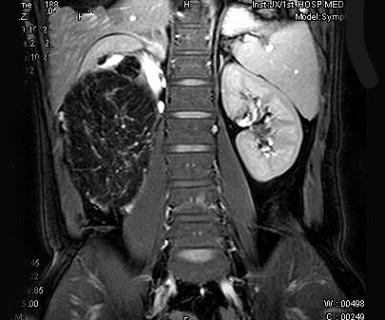

问题 男,30岁。右侧腹部包块渐增大,伴胀痛1年余。MRI检查见巨大包块,最可能的诊断是 ( )

选项 A、右肾巨大血管瘤 B、右肾错构瘤 C、右肾髓样脂肪瘤 D、右肾畸胎瘤 E、右侧肾上腺腺瘤

答案 C